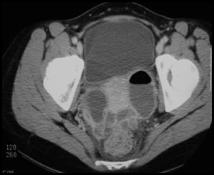

Bilateral tubo-ovarian abscesses with gas

Right                                                             Left